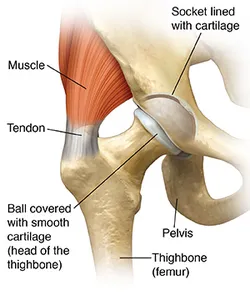

A healthy hip

In a healthy hip, smooth cartilage covers the ends of the thighbone, as well as the pelvis where it joins the thighbone. This allows the ball to glide easily inside the socket with little friction. When the surrounding muscles support your weight and the joint moves smoothly, you can walk painlessly.